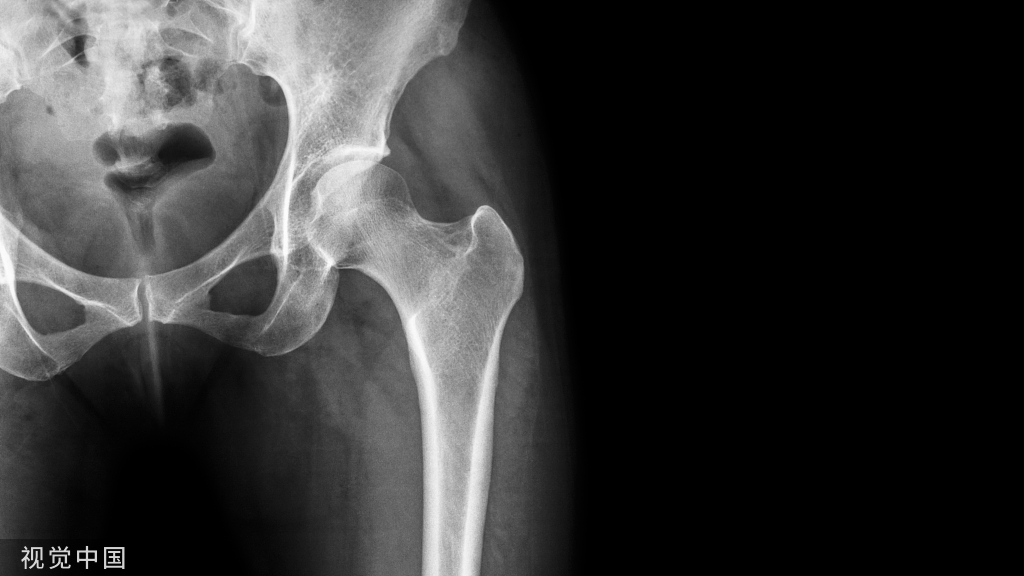

近端指骨骨折

1.经关节内技术手术方法:在 MCP 关节上作一 3.0mm的切口。MCP关节屈曲70°,在透视下自 MCP 关节背侧插入一根导丝。为方便导线的插入,将近节指骨的基部推向背侧、形成背侧半脱位。由于关节囊和副韧带的收紧,MCP关节的90°屈曲位可以防止近节指骨的背侧移位。然后将线沿其纵轴推进到近节指骨的基部。然后插入 3.0 mm 或 2.2 mm 无头加压螺钉(图 3)。在 MCP 关节半脱位困难的情况下,导丝也可以在不侵犯关节的情况下,在近节指骨基底部斜行插入。

图3 近节指骨的顺行无头加压螺钉(IMCS)固定。2.顺行经关节技术当近节指骨无法实现足够的背侧半脱位导丝位置不理想时,建议采用经关节技术。在MCP上作一长3.0mm的切口,屈曲 90°。导丝插入掌骨头的背侧。然后将导丝通过掌骨推进到近节指骨的远端(图 4)。

图4 近节指骨顺行髓内无头加压螺钉 (IMCS) 固定的经关节技术(通过掌骨头)。该技术的缺点在于会损伤掌骨头的软骨和近节指骨的基底部

图5 经关节内与顺行经关节固定模式图。3.逆行经关节内技术除顺行置入螺钉外,也可通过近指间关节逆行置入IMCS。在屈曲 90° 的近端指间 (PIP) 关节上做一个 3.0 mm的切口。然后将导丝沿其纵轴推进到近节指骨的基底部(图 6)。该技术操作较为简单,但同样存在损伤指骨远端关节面软骨风险,同时容易损伤伸肌腱

图6 近节指骨的逆行IMCS 固定。4.双顺行经关节内技术与掌骨类似,粉碎的指骨骨折采用单一加压螺钉固定同样有固定不牢靠风险。对这一类骨折,类比掌骨骨折的“Y” 型支撑技术,可采用双顺行IMCS固定(图 7) 。手术方法:在 MCP 关节上做一个横向切口,然后屈曲 70°。将指骨的近端向背侧半脱位,以便在透视下插入第一根导丝。然后可以在与指骨的长轴倾斜的方向上插入第1根导丝。最后,将第二颗螺钉置于更倾斜的方向,且螺钉长度需更短。我们通常使用2枚2.2 mm无头加压螺钉。

图7 双顺行经关节内固定近节指骨骨折。

对于粉碎的近节指骨骨折,如加压过度可能导致短缩,也可采用单枚螺钉固定。

图8 近节指骨粉碎骨折的单枚螺钉固定。